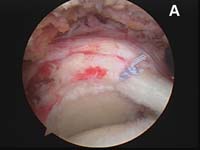

- the rotator cuff tear is identified and loose, degenerated, and frayed tissue around the cuff edge must be removed back to healthy tissue. This process is called débridement.

- The edge of the cuff tear must be brought back to its normal position without undue tension. This process is accomplished using techniques called mobilization or in larger tears, a technique called margin convergence. (See Fig. 4).

- The tear must be fixed into place using specially-designed suture anchors that allow the surgeon to approximate the cuff tear securely to the bone.